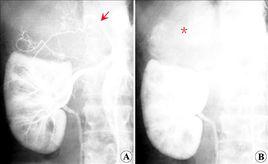

2.按腹主動脈、腎動脈、膈下動脈、腎上腺上、中、下動脈順序依次造影。

3.注射參數包括腹主動脈造影對比劑用量35~40ml/次,注射流率15~20ml/s;腎動脈造影對比劑用量10~15ml/次,注射流率5~7ml/s;膈下動造影對比劑用量6~8ml/次,注射流率3~4ml/s。腎上腺上、中、下動脈造影對比劑用量4~6ml/s,注射流率1~2ml/s。

4.造影體位為正位。

5.造影程式為2~4幀/s,注射延遲0.5s。屏氣狀態曝光至靶器官微血管期和靜脈早期。